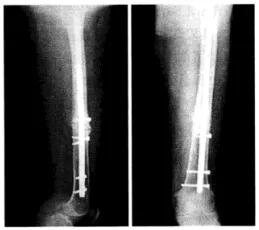

股骨干骨折髓内钉固定后骨不连,应用阻挡螺钉技术(Poller技术)再固定